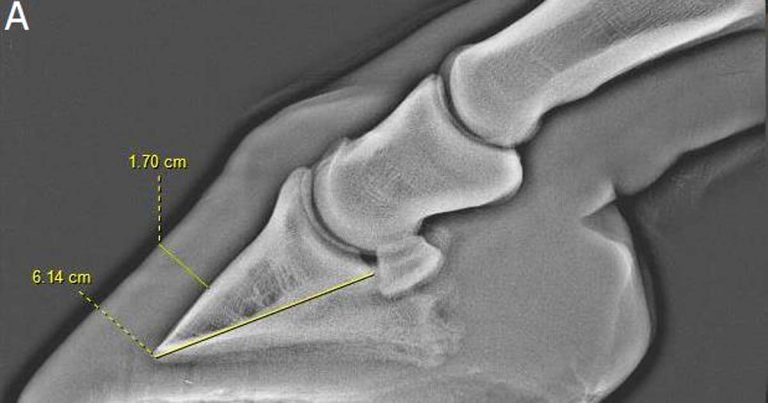

Figure 1. Lateromedial radiographs of the front feet of an 11-year-old Connemara-cross gelding. The horse was overweight and short stepping in front when ridden. Bilateral perineural analgesia of the palmar nerves (at the base of the proximal sesamoid bones) resulted in marked improvement in the forelimb step length. 1a. The left front foot. The hoof distal phalanx distance to palmar length of the distal phalanx ratio was 27.7 per cent. 1b. The right front foot. The hoof distal phalanx distance to palmar length of the distal phalanx ratio was 27.4 per cent. Mild modelling at the toe of the distal phalanx is apparent. In both feet, loss of the normal radiolucent halo around the distal phalanx in the toe region and mild distal rotation of the distal phalanx occurred. The radiographic findings are suggestive of laminar pathology and it was concluded this horse had atypical laminitis – most likely as a result of abnormal bodyweight and insulin resistance.

Radiographic assessment of the dorsal hoof wall in relation to the distal phalanx is important in the evaluation of laminitis. Subclinical laminitis may be under-diagnosed compared with the conventional acute formof disease.

Subclinical laminitis can contribute to poor performance, resulting in loss of extravagance of forelimb movement or a bilaterally shortened forelimb step length. It may be insidious in onset, with radiographic changes associated with the distal phalanx or hoof wall (Figure 1; Mansmann and Castelijns, 2017).

Alteration of the hoof wall in suspected subclinical laminitis has been described in Thoroughbred racehorses (Linford et al, 1993). However, a lack of data exists about subclinical laminitis in sports horses. Mullard et al (2016) retrospectively reviewed lateromedial foot radiographs of 279 horses (415 feet) without a history or clinical signs of typical laminitis. A wide range was apparent in the ratio between the hoof wall distal phalanx distance to the palmar length of the distal phalanx, mean 0.25 plus or minus 0.03 (median 0.25; interquartile range = 0.23 to 0.26; range = 0.19 to 0.36).

Breed, age and height:bodyweight ratio had a significant effect on the ratio, although did not adequately account for the variability in the ratio within this population, which may be associated with subclinical laminitis.

A higher frequency was apparent of modelling of the toe of the distal phalanx in horses in which the ratio was greater than 26%, compared with those where the ratio was less than or equal to 26%. No association existed between dorsal hoof wall thickness and the presence of divergent growth rings on the hoof wall, but no horse had divergence greater than 3mm.